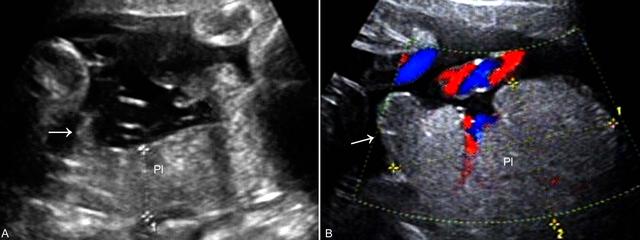

2D-US时边缘性轮状PL可能没有明显异常发现,在适当的断面上显示PL边缘不规则隆起时应当考虑部分性轮状PL或轮状PL的可能(图3)。需要注意的是,有时卷曲的PL边缘在2D-US时在某些断面上可能显示为羊膜腔无回声区内的PL边缘的带状突起回声(图3A),或可能误诊为羊膜束带或宫腔粘连。通过全面的检查或3D-US有助于显示PL轮状化的程度。

图3轮状胎盘声像图

2D-US显示轮状PL后要注意对胎儿进行全面检查和评估,以排除胎儿可能存在的异常。